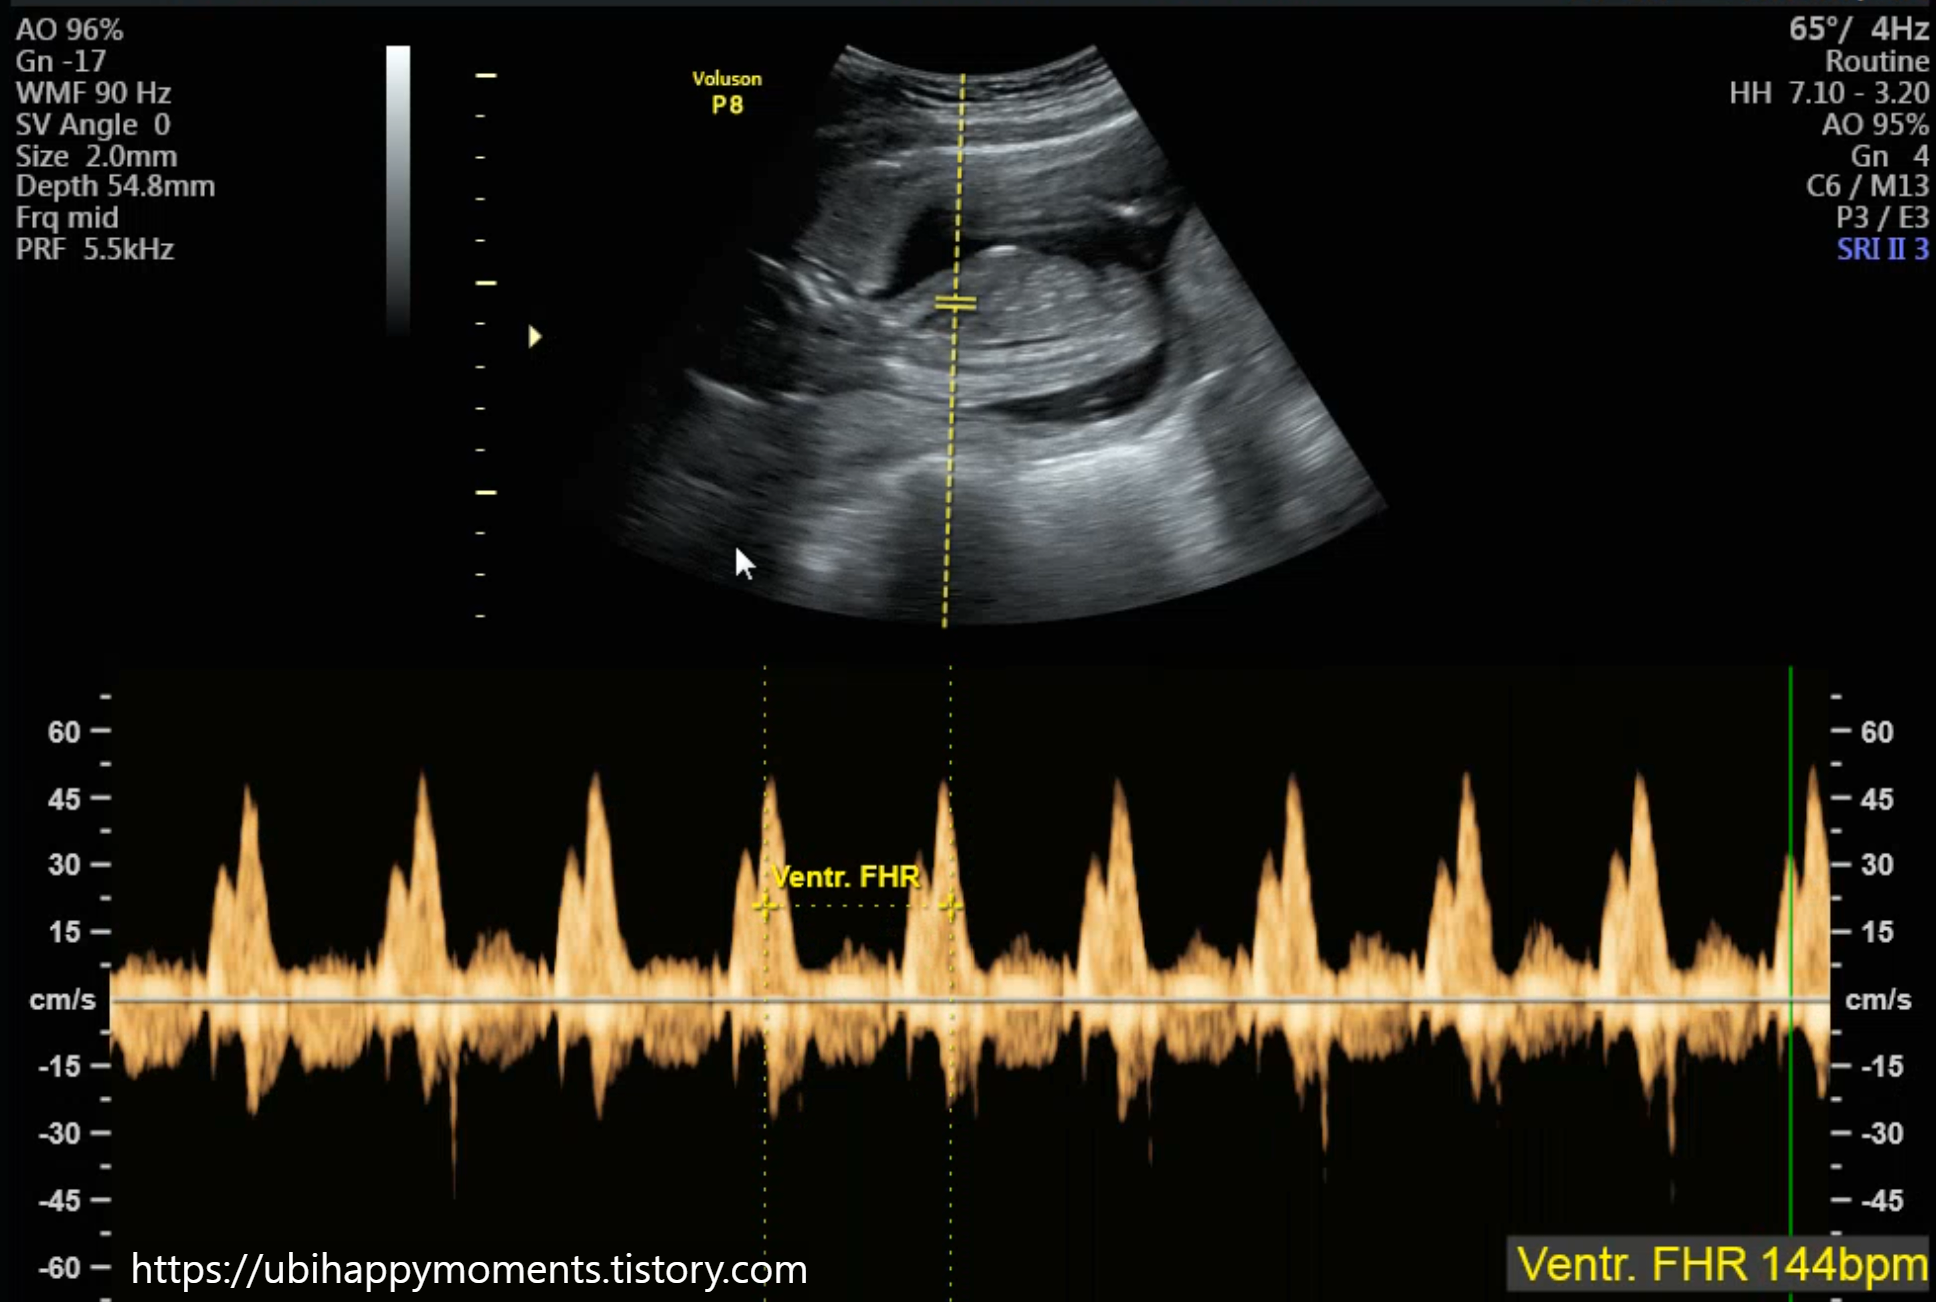

16주 차에 2차 기형아 검사를 받았습니다!

'초음파 검사'를 통해

태아의 신체적인 기형이 있는지 없는지 확인합니다.

2차는 일반 초음파로 확인하더라고요!